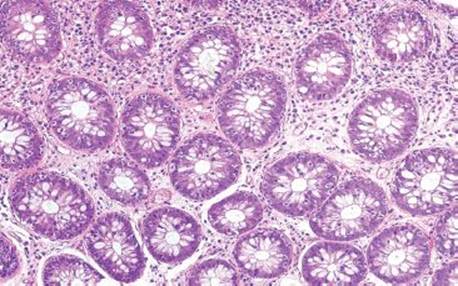

Figure 2.134 Lymphocytic gastritis pattern, common variable immunodeficiency (CVID). Lymphocytic gastritis is associated with a number of immune mediated disorders. In this example, the gastric biopsy is from a patient with CVID. Mild intraepithelial lymphocytosis and intestinal metaplasia are seen (bracket). Careful examination of the lamina propria reveals a marked paucity of plasma cells, consistent with the established diagnosis of CVID.